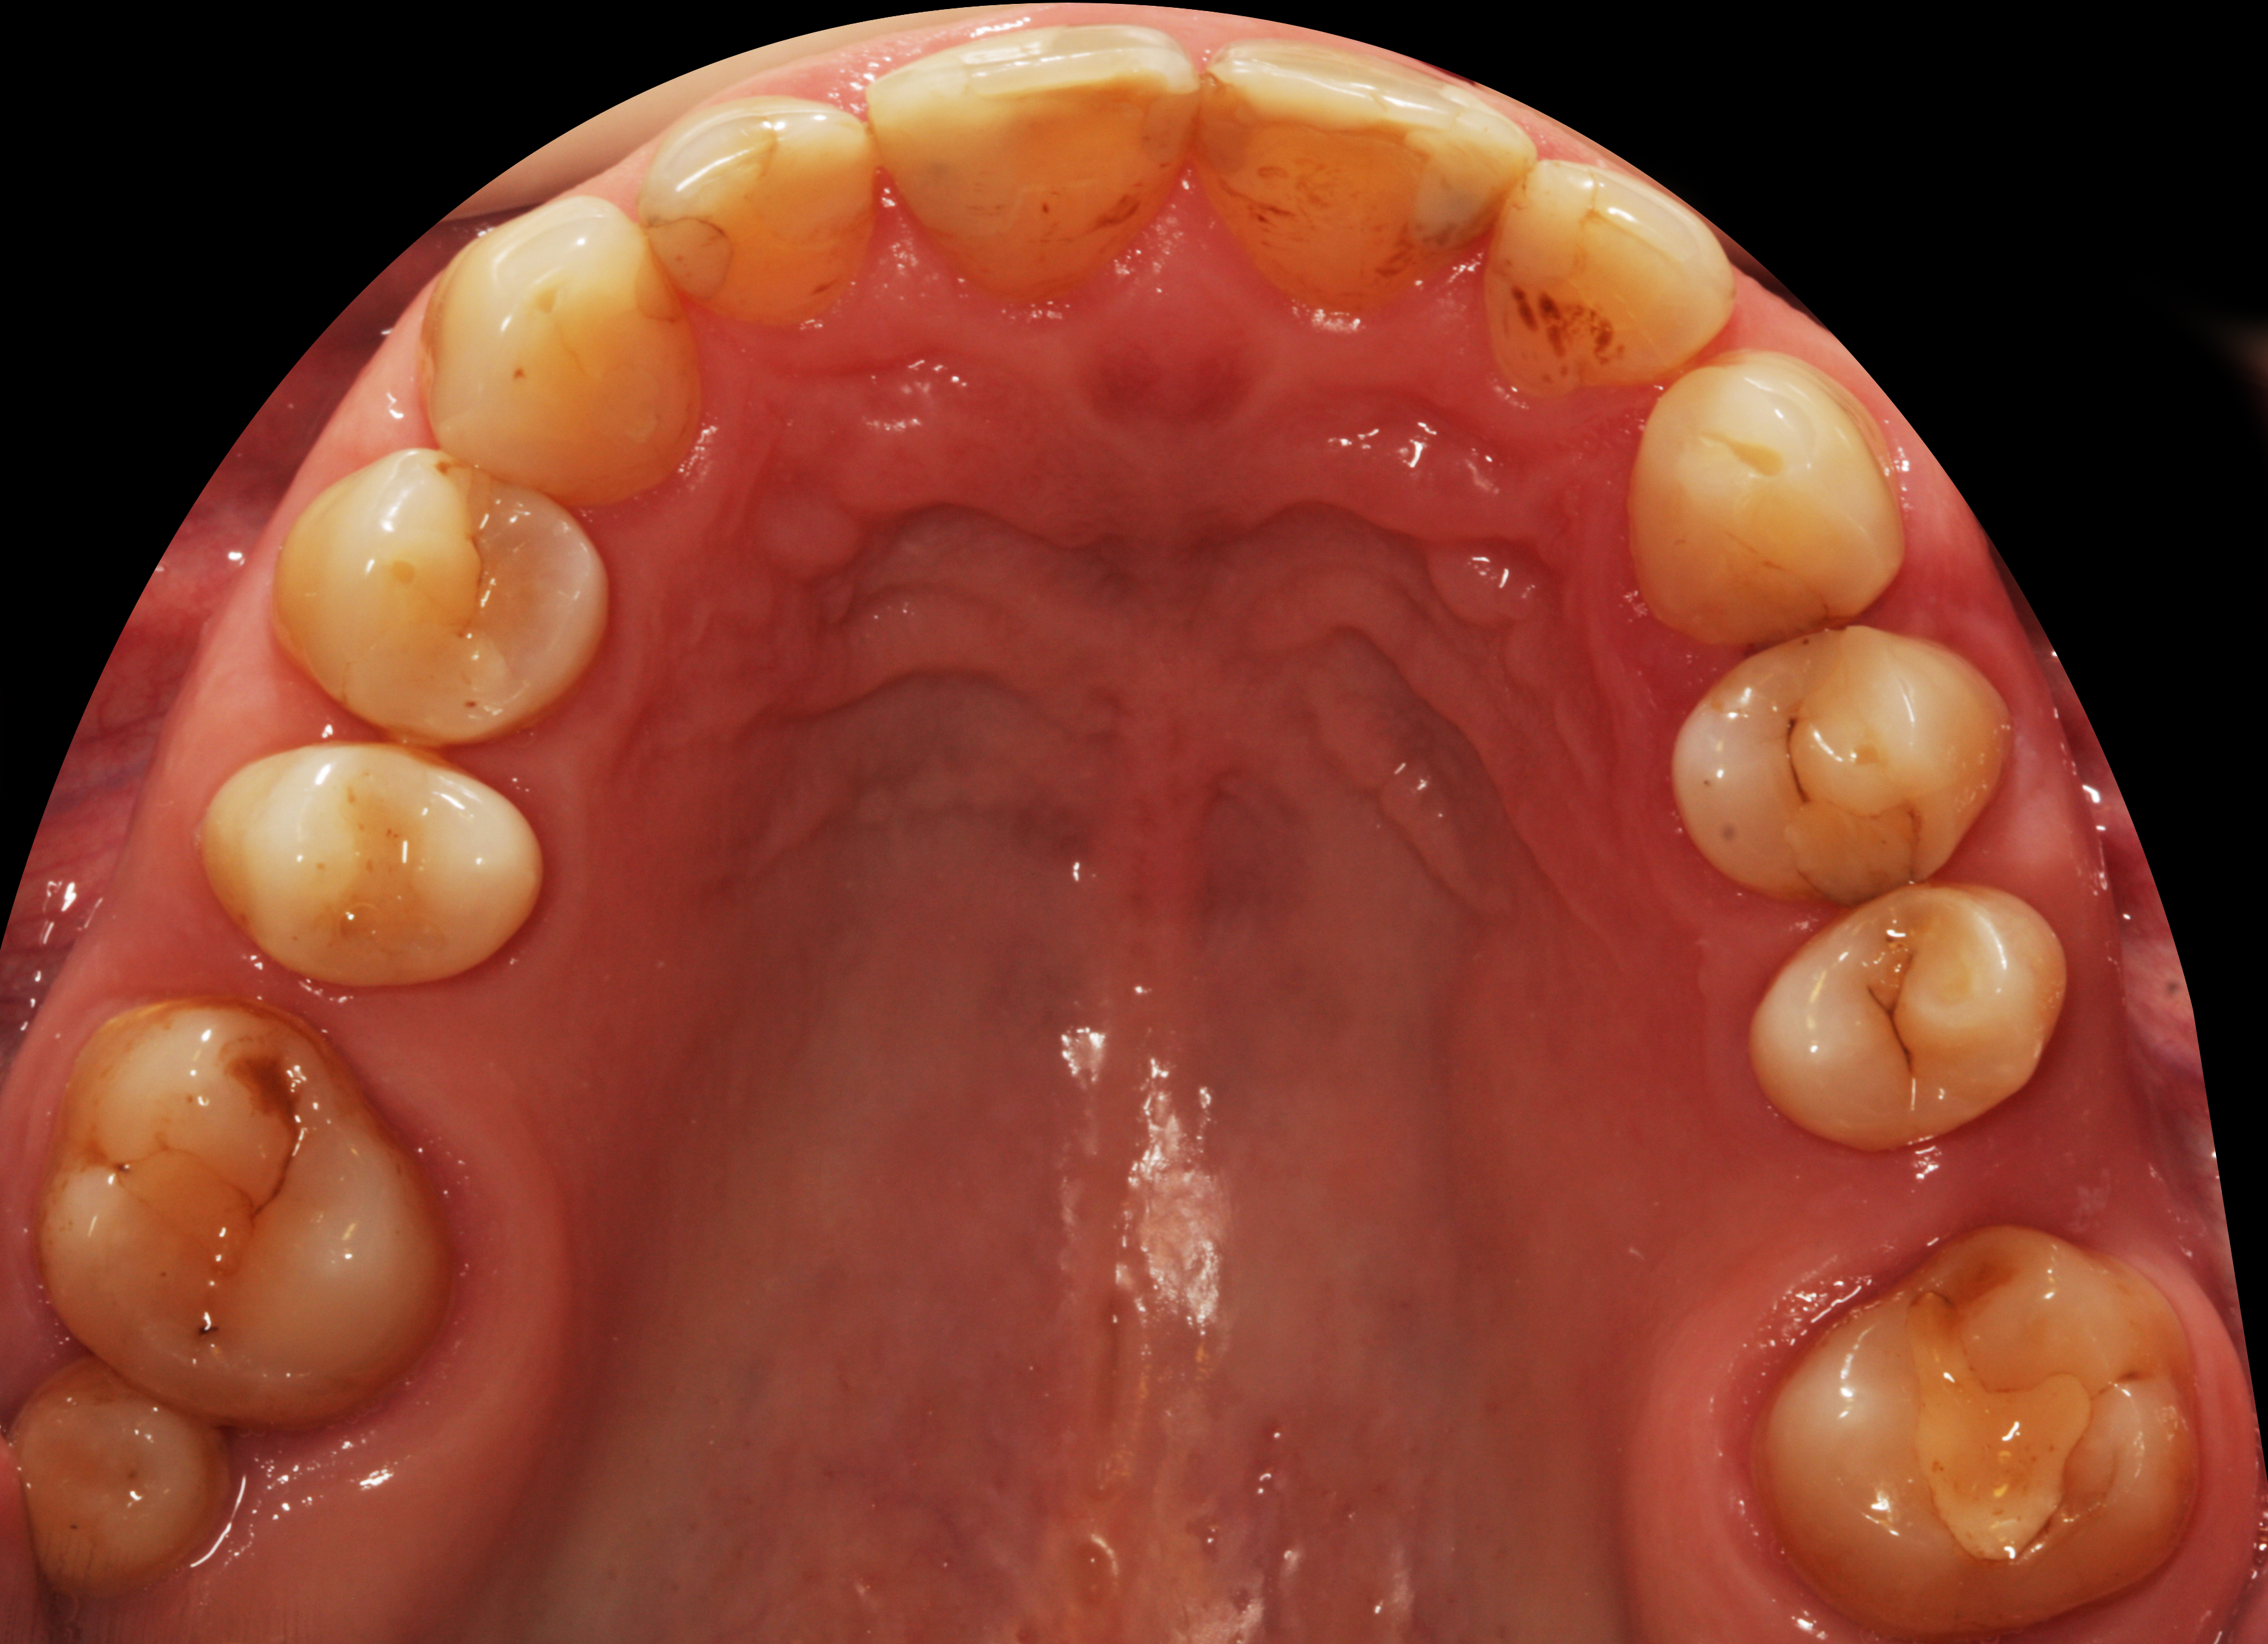

Do kliniki Stomatologia Bez Bólu zgłosiła się pacjentka, lat 61 z problemem nadwrażliwości zębów. Po przeprowadzonym wywiadzie stwierdzono spożywanie sporej ilości sezonowych owoców (truskawki, wiśnie, czereśnie, czarna porzeczka), nawet 3 razy dziennie. Następnie wykonano badanie wewnątrzustne. Stwierdzono obecność płytki nazębnej, ciemnego osadu oraz kamienia nazębnego na części trzonowców: